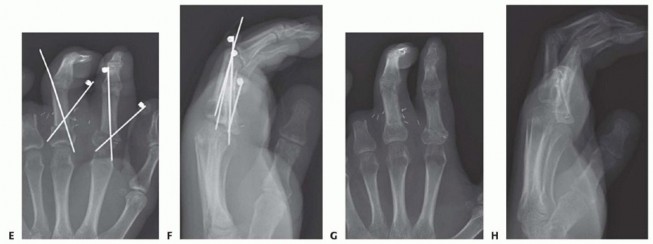

TECH FIG 3 • A-D. Parallel longitudinal K-wires allow for easy and rapid fixation with low complication rates.(continued)

TECH FIG 3 •(continued)E-H. In more proximal amputations, longitudinal K-wires may not be possible. Crossed K-wires can be used successfully in these injuries.

A survival rate greater than 80% is expected for replantation surgery.Functional outcomes are greatest for replantation of the thumb, proximal hand, and single digit distal to the FDS insertion (FIG 6A-D).5,6,13,16Recovery of sensation is correlated with function. As in other peripheral nerve injuries, age is the most important factor for recovery, with better results in younger patients. The average two-point discrimination inreplanted thumbs is 11 mm and in fingers is 8 mm.4 These values represent the average recovery for sharp amputation. Crush and avulsion mechanisms result in poorer two-point discrimination.Range of motion is related to level of amputation. Active PIP joint motion in replantations proximal to the FDS insertion average 35 degrees, whereas replantations distal to the FDS insertion result in 82 degrees of PIPjoint motion (FIG 6E-G).7

FIG 6 • A-D. This patient sustained an amputated thumb, which was successfully replanted with good cosmetic and functional results. E-G. Successful replantation of the ring and small fingers resulted in a functional hand capable of holding common objects. Vigilant reexamination of color, warmth, turgor, and capillary refill is necessary to decide whether exploration in the operating room is indicated. Revisions after 4 to 6 hours of reduced perfusionseldom result in digit salvage.7If venous engorgement occurs postoperatively, elevate the hand and remove constrictive dressings (including sutures that are too tight).Consideration for return to the operating room is based on intraoperative findings affecting the possibility of revising the venous anastomosis.If this is not possible, leeches or nail removal are used to alleviate venous congestion. These methods typically are used to bridge the first 4 to 6 days until adequate outflow is established.